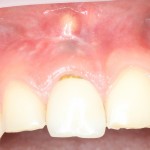

Все началось с воспаления, свищевого хода и удаления зуба:

Затем, мы готовим лунку и проверяем позиционирование импланта: